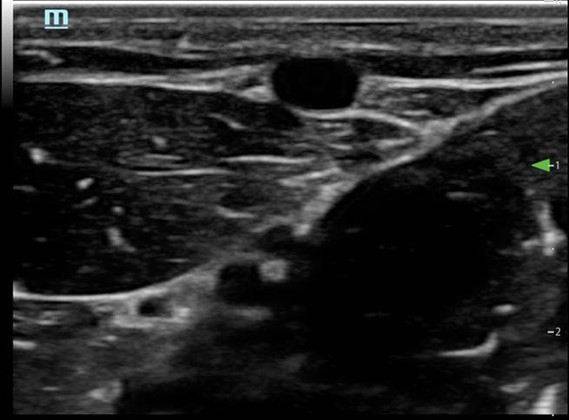

- Visualize the vein in cross-section (Fig. 3)

Figure 3. Short axis approach: vein visualized in cross axis